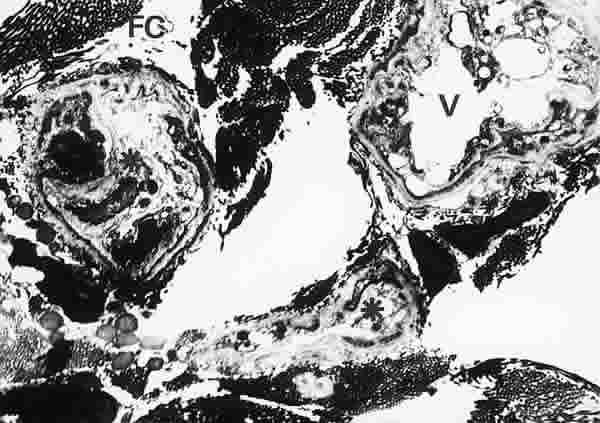

Figura 23

BIOPSIA EN UN PACIENTE CON SS1-GRADO III. SE OBSERVAN VASOS CAPILARES (V), PRÓXIMOS A LA GLÁNDULA LAGRIMAL, MUY ALTERADOS, CON ESTRUCTURAS DE NEOFORMACIÓN DE VASOS SANGUÍNEOS (*). LAS FIBRAS DE COLÁGENO (FC) SON MUY ABUNDANTES. MICROSCOPIA ELECTRÓNICA. MAGNIFICACIÓN ORIGINAL X4000.